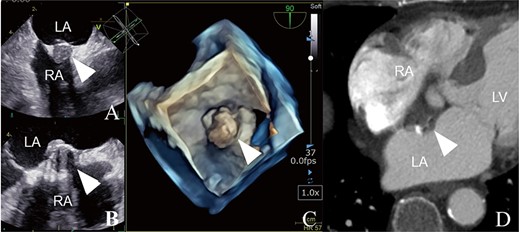

An 84-year-old woman was referred to our institution because of an IAS tumor detected on follow-up echocardiography (Fig. 1A). She had a history of acute myocardial infarction (MI) at the age of 73 years. Although she had few coronary risks, the left anterior descending (LAD) artery was totally occluded at the proximal segment (Fig. 1B). Further, no arteriosclerosis was found in other coronary arteries (Fig. 1C). Percutaneous coronary intervention was successfully performed, and follow-up coronary arteriography (CAG) showed no restenosis (Fig. 1D). She had no symptoms of congestive heart failure or murmur; however, transthoracic echocardiography incidentally revealed an IAS tumor presenting as a solid and immovable mass of 14 × 16 × 12.1 mm, while transesophageal echocardiography showed an IAS solid tumor with calcification (Fig. 2A–C). Enhanced computed tomography revealed a low-density area with a spot of high density, leading to suspicion of a cardiac cyst, thrombus or myxoma (Fig. 2D). Our cardiac team concluded that tumor pathological examination was necessary for an accurate diagnosis.

Preoperative examination findings (A–C): trans-esophageal echocardiography findings. (D) Enhanced computed tomography findings. Each image shows an IAS tumor with a solid mass and calcification suggesting a thrombotic IAS tumor (arrowheads). LA, left atrium; RA, right atrium; LV, left ventricle.